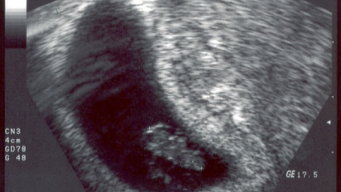

In the first trimester, pregnancy ultrasound is performed to check the fetal heartbeat, visualize the gestational sac, and determine gestational age. In some cases, when done very early, before 7 weeks, the ultrasound does not show any details and the heartbeat may not be heard.

It is also indicated to rule out a possible ectopic pregnancy, which happens when the embryo begins to develop outside the uterus or in the case of a molar pregnancy. The ultrasound can show an abnormal placenta and an irregular embryo.

Between 11 and 14 weeks of pregnancy, a new ultrasound will be requested. This is called the nuchal translucency scan, which measures the skin fold at the back of the neck and checks for the presence of the nasal bone. This ultrasound can detect genetic issues, such as Down syndrome. If any changes or suspicions are found during the ultrasound, the obstetrician may order further tests for confirmation, such as chorionic villus sampling or amniocentesis.